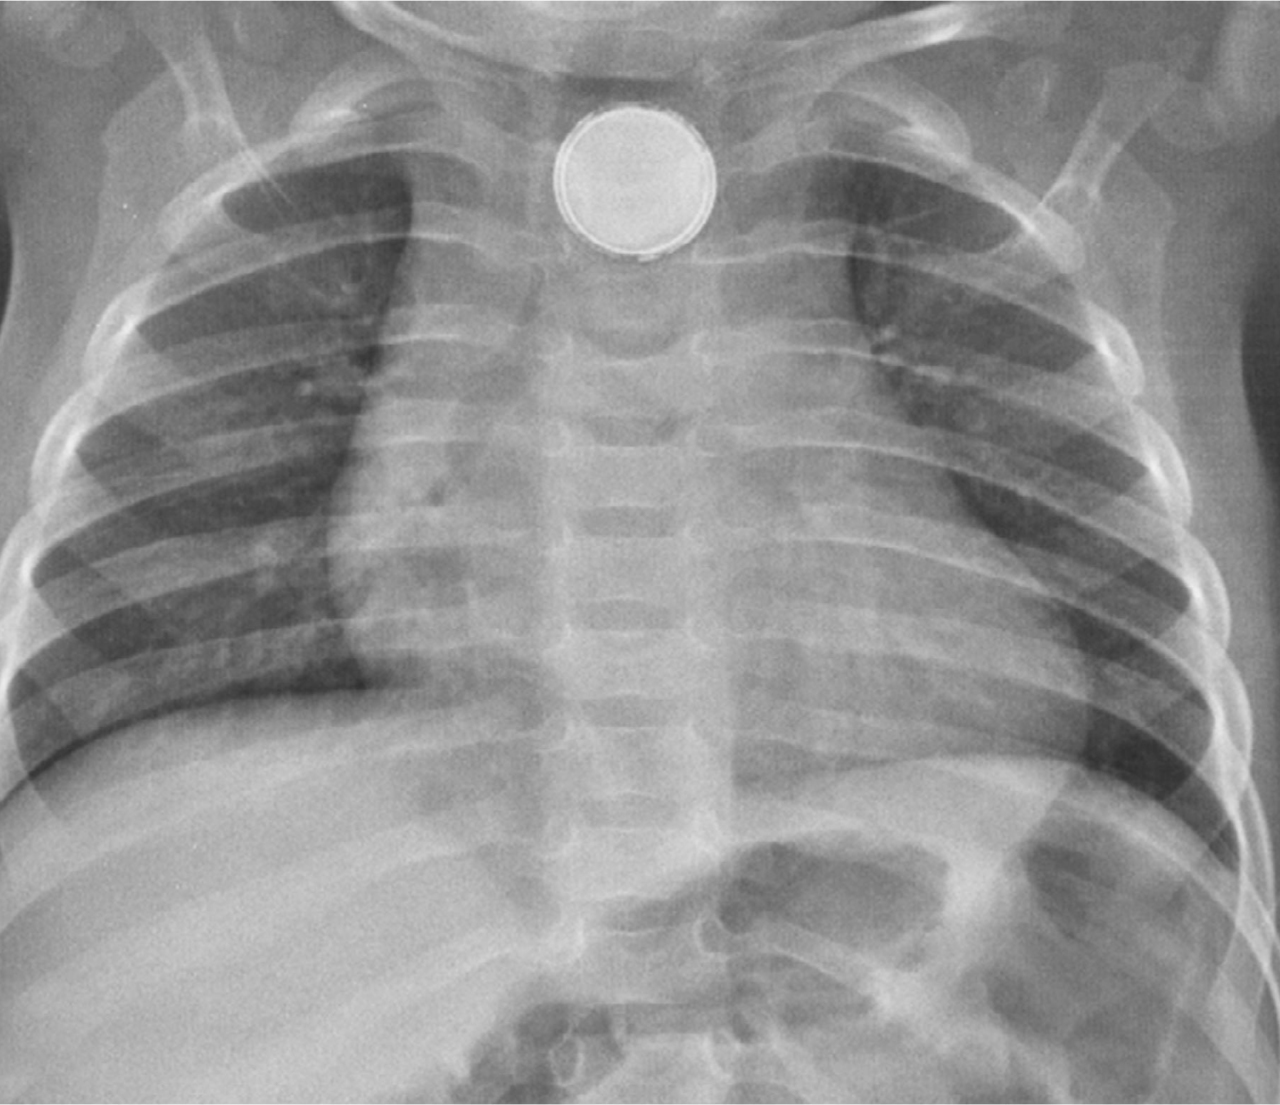

Question 4 : Voici la radiographie du thorax de l’enfant. Interprétez-la.

Surtout sur la radiographie de profil, nous pouvons bien voir que la trachée est en avant du corps étranger

Sur la radiographie de profil, on voit que le corps étranger est sur le trajet de l’œsophage0

Sur la radio de face, les deux poumons ont la même taille. Rappel : le trapping se voit sur une radiographie en expiration où l’air n’arrive pas à sortir du côté bloqué

Signe très important : les piles boutons ont un double contour (sur les radios de face) et une petite marche d’escalier sur le contour (sur les radios de profil)

Il n’y a pas de double contour sur une pièce de monnaie

Il s’agit ici d’un corps étranger œsophagien. Un corps étranger œsophagien peut avoir causé un syndrome de pénétration initialement par deux mécanismes possibles : soit le corps étranger a entraîné une cyanose en bloquant le larynx lors de son passage dans l’hypopharynx avant la déglutition, soit il y a eu une véritable inhalation, puis expulsion lors d’un effort de toux et déglutition. C’est ce qu’il se passe dans la majorité des cas de syndrome de pénétration avéré avec fibroscopie bronchique blanche : le corps étranger a été expulsé, puis recraché ou dégluti.

La grande crainte lors d’un corps étranger œsophagien est la pile bouton, qui peut faire des dégâts irréparables en quelques minutes sur la muqueuse œsophagienne par contact. Elle peut être différenciée à la radio d’une pièce de monnaie (corps étranger beaucoup plus fréquent), grâce au double contour que l’on aperçoit facilement sur les radios de face et de profil. Une pièce de monnaie présente un contour lisse. Insérer image « Figure3.jpg ».